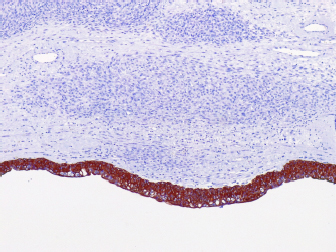

Similar to the findings in human medicine (Chen et al., 2008), malignant neoplasms in the urinary tract are commonly located in the distal portion of the ureter (Berzon, 1979; Hanika & Rebar, 1980; Polit et al., 2020), whereas benign neoplasms affect the proximal region (Hattel et al., 1986; Burton et al., 1994). In the present report, the ureteral leiomyosarcoma was located in the proximal ureter. The exact location of the neoplasm was obtained only through exploratory laparotomy because the abdominal ultrasound was inconclusive, and the owner declined computed tomography. Furthermore, normal urothelial mucosa in the ureter was observed by IHC for pan-cytokeratin (Fig. 5), whereas below the urothelial mucosa, mesenchymal cell proliferation was negative. In the histopathological examination, it was also possible to determine that in the kidney sample, we did not have neoplastic cells, whereas in neoplastic tumors, the intact ureter epithelium was present, indicating a urinary origin and possibly an origin from the ureteral wall, as we did not observe any other structures that would suggest neoplastic tissue originating from the kidney.

Fig. 3. Photomicrographs of a canine ureteral leiomyosarcoma. (A) Positive staining for GATA3 in normal urothelial mucosa in the ureter, 20x. (B) Staining for UPIII in normal urothelial mucosa in the ureter, 20x. (C) Positive staining for alpha-smooth muscle actin (1A4) in neoplastic cells, 10x. (D) Positive staining for muscle-specific actin, 10x. (E) Positive staining for smooth muscle myosin heavy chain, 40x. (F) Scatted positive staining for desmin, 10x. IHC, Harris hematoxylin counterstaining.

Fig. 5. Photomicrographs of a canine ureteral leiomyosarcoma. (A) Positive staining for pancytokeratin (AE1AE3) in normal urothelial mucosa in the ureter with negative staining of mesenchymal cell proliferation below, 10x.